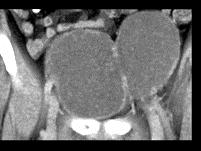

男,72岁,尿频,请根据所示图像作出最可能诊断 ( )A、膀胱癌B、输尿管癌C、先天性巨输尿管D、膀胱憩室E、输尿管囊肿

问题 男,72岁,尿频,请根据所示图像作出最可能诊断 ( )

选项 A、膀胱癌 B、输尿管癌 C、先天性巨输尿管 D、膀胱憩室 E、输尿管囊肿

答案 D